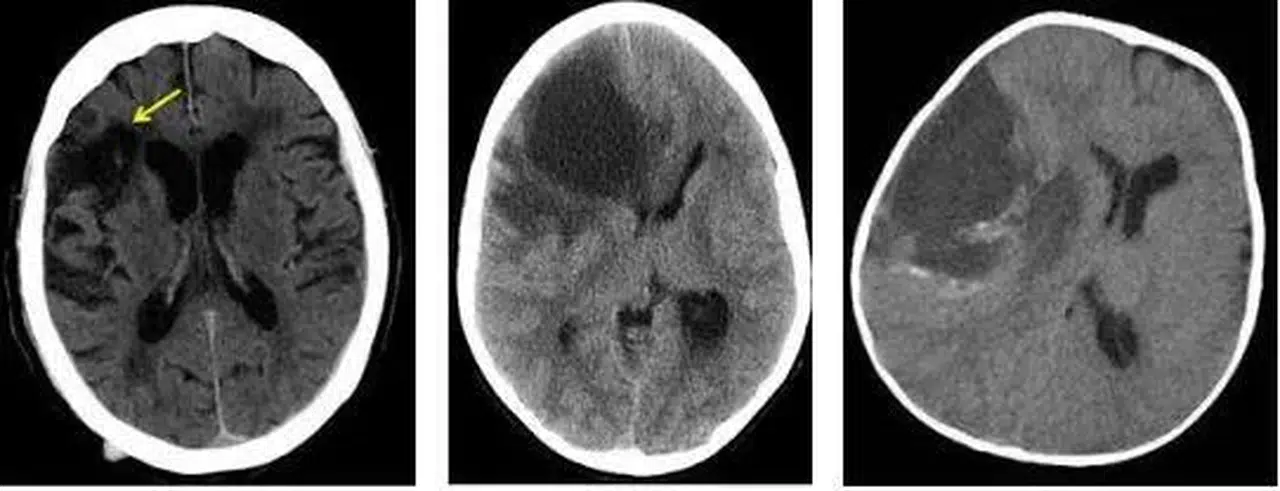

Beyinde hipodens lezyon

Örneğin beyinde hipodens alan, bazen eski bir damar tıkanıklığını gösterebilirken; karaciğerde hipodens lezyon çoğu zaman basit bir kist olabilir. Ancak her hasta için değerlendirme farklıdır.